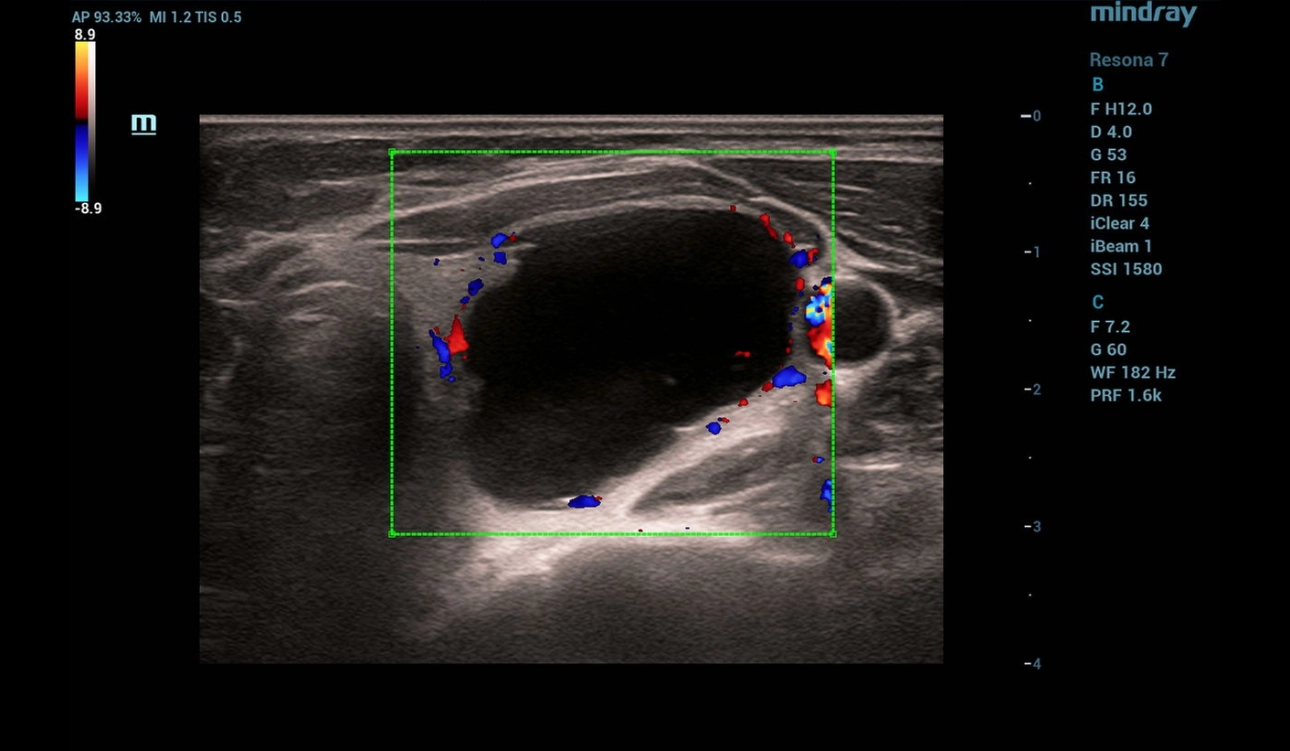

B-mode and Color Flow Doppler (CFD)

Ultrasonography was performed on a Resona 7 ultrasound machine (Mindray, China) using a linear probe L14-5WU. A cystic focal mass of anechogenic structure measuring 24x28x38 mm with smooth clear contours was detected in the left lobe of the thyroid gland (Fig. 1, 2)

In Color Flow Doppler (CFD) there is no blood flow in the focal mass with the presence of single perinodular vessels (Fig.2)

Figure 2. CFD image of thyroid